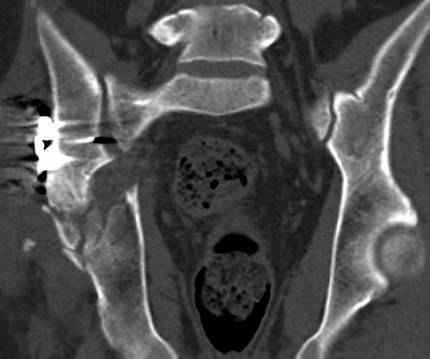

высылаю дополнительно сканы.

итак, второй вариант: высокий двухколонный с вовлечением КПС... Ни одно из основных повреждений не репонировано, кроме задней стенки. Скорее всего попытка реконструкции вертлуги сейчас будет очень травматичной и не очень эфективной, т.е. вероятный риск более значим, чем ожидаемая польза... Лучше подождать, и потом сразу эндопротез